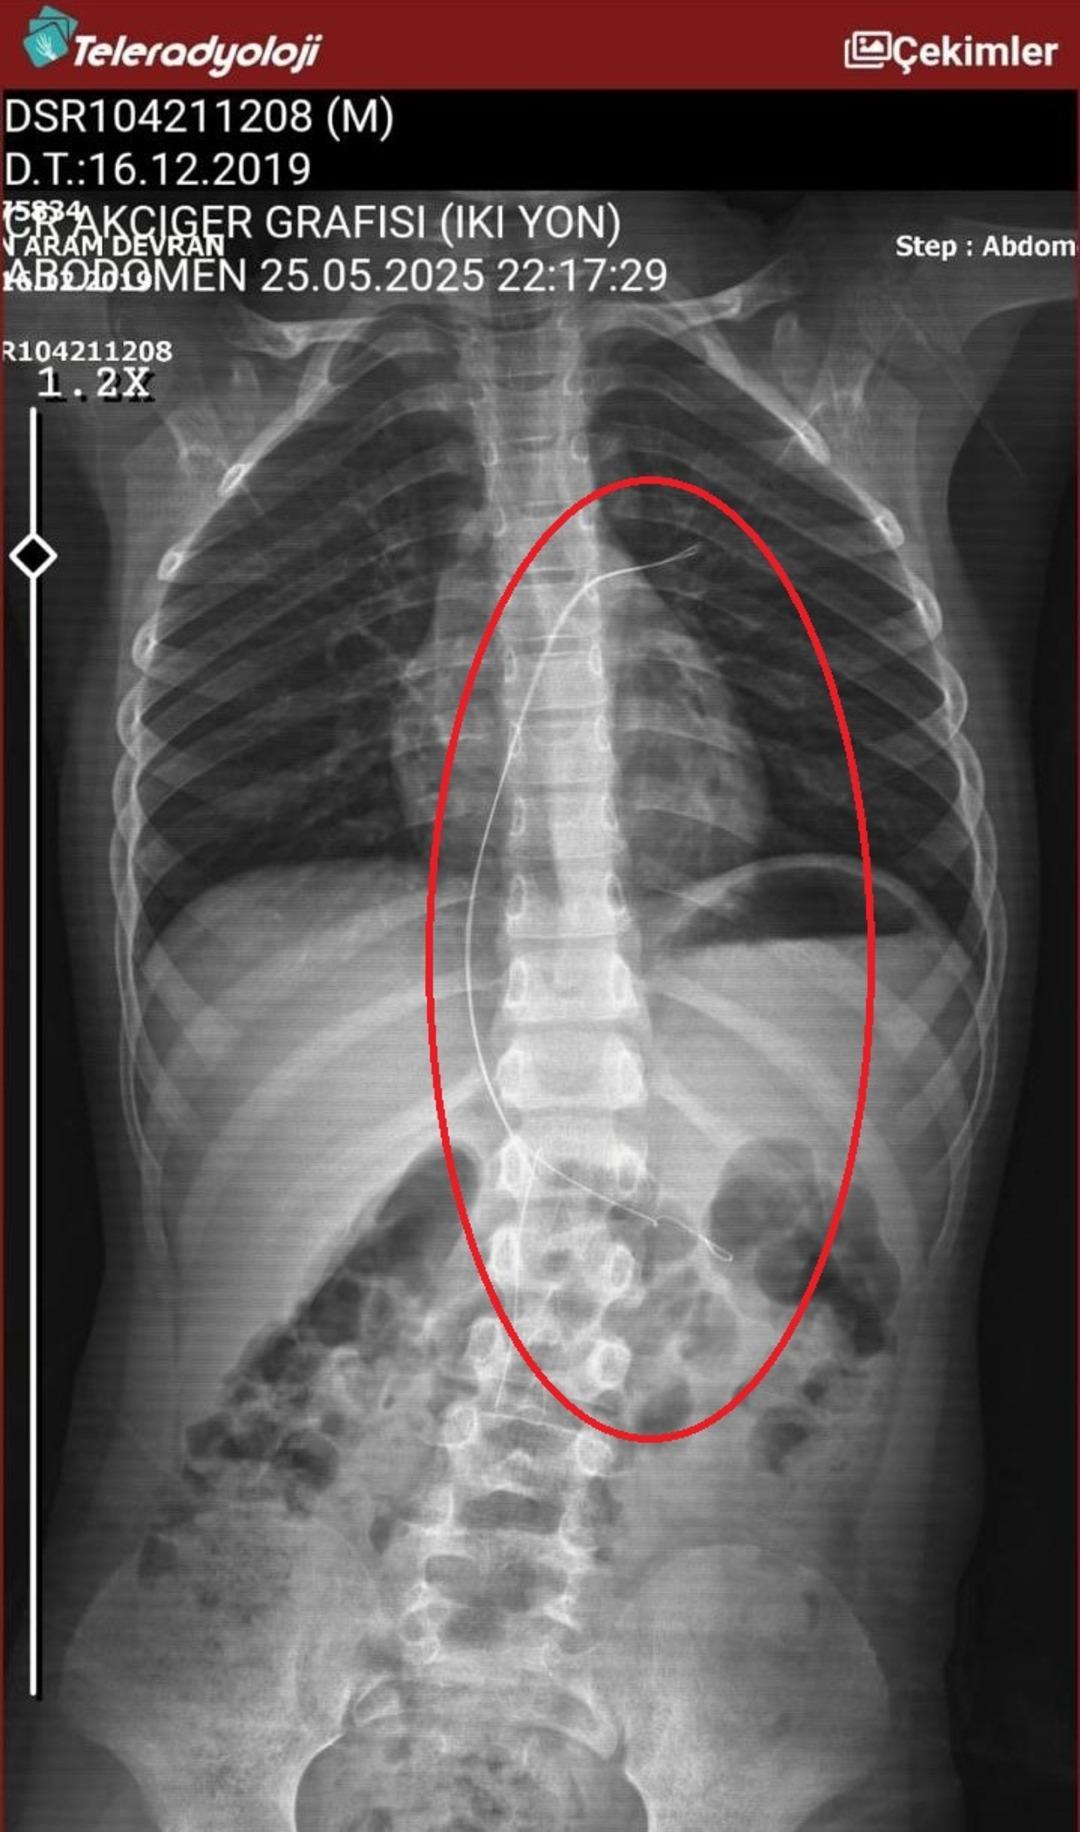

Seamore (37) ve Şaç'ta yaşayan Mehmet Ötün (40), Mayıs ayında bir parça salatalık yuttuktan sonra öksürük ve kusma şikayetleri gözlendiğinde Sernak Eyalet Hastanesine getirildi. Burada, ARAM gövdesinde yarıçap X ve manyetik rezonans görüntüleme unutuldu. Diyarbakir Gazi Yeşargil'in eğitim ve araştırma hastanesi jinekolojiye ve ARAM'lar için ek binaya yönlendirildi, 18 santimetrede 5.5 saatlik riskli cerrahi kaldırıldı. Postoperatif araştırmalarda, kateter kalp kapakına ve karaciğere zarar vermeye kararlıydı.

“Oğlum yaklaşık 5.5 saat ameliyatta kaldı. Müdahaleye giren doktor olumsuz bir şekilde serbest bırakıldı. Yorgun ve yorgun olduklarını söylüyordu. Materyal geliyor, iplik geliyor, dedi. Bir doktor çıktı, 'İki seçeneğimiz var. Hayatım için çok acı vericiydim.